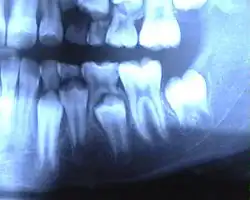

Панорамная рентгенограмма зубов: видны закладки постоянных зубов под прорезавшимися молочными, справа на схеме — белым окрашены молочные зубы, тёмные — закладка постоянных зубов в челюсти

Зачаток постоянного зуба отделен от корня молочного тонкой костной пластинкой. С развитием зачатка постоянного зуба последний начинает давить на костную перегородку. В окружающей соединительной ткани появляются остеокласты, которые и разрушают эту перегородку. Далее процесс начинает идти с двух сторон — с поверхности корня с помощью остеокластов и со стороны пульпы. Пульпа молочного зуба постепенно превращается в грануляционную ткань, богатую кровеносными сосудами и остеокластами, которая разрушает дентин. Процесс заканчивается полным рассасыванием корней молочных зубов, оставляя одну коронку, которую легко удаляют иногда сами дети или выталкивает растущий постоянный зуб. Прорезывание постоянных зубов не сопровождается какими-либо болезненными изменениями со стороны организма ребенка, как это наблюдается в период прорезывания молочных зубов. Исключение составляют зубы мудрости, которые прорезываются в возрасте от 17 до 25 лет и старше.